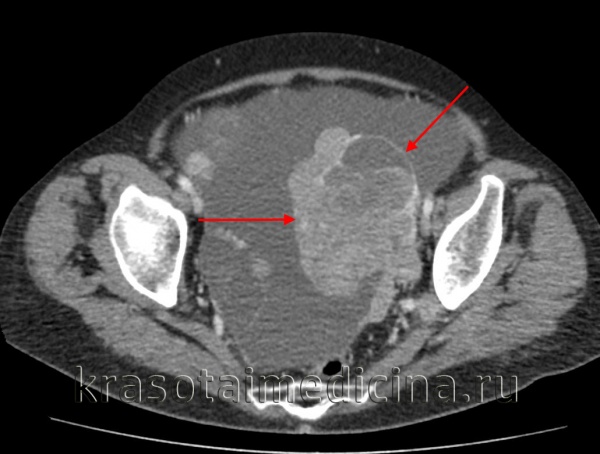

- Методы визуализации. С помощью трансвагинальной эхографии (УЗИ), МРТ и КТ малого таза выявляется объемное образование неправильной формы без четкой капсулы с бугристыми контурами и неодинаковой внутренней структурой; оцениваются его размеры и степень распространенности.

Трансабдоминальное УЗИ и трансвагинальная эхография в 96% случаев позволяют дифференцировать доброкачественные опухоли яичников от миомы матки, воспалительных процессов в придатках. В нетипичных случаях показано проведение компьютерной и/или магнитно-резонансной томографии.

Дополнительно может назначаться рентгенография органов грудной полости, КТ и МРТ таза, брюшной полости, колоноскопия, пункционная биопсия дугласова пространства (для исключения рака). Дифференциальная диагностика проводится с первичным и метастатическим овариальным раком, доброкачественными опухолями, ретенционными кистами яичников, опухолями матки (чаще с миомой, саркомой) и кишечника, гнойными воспалениями придатков.